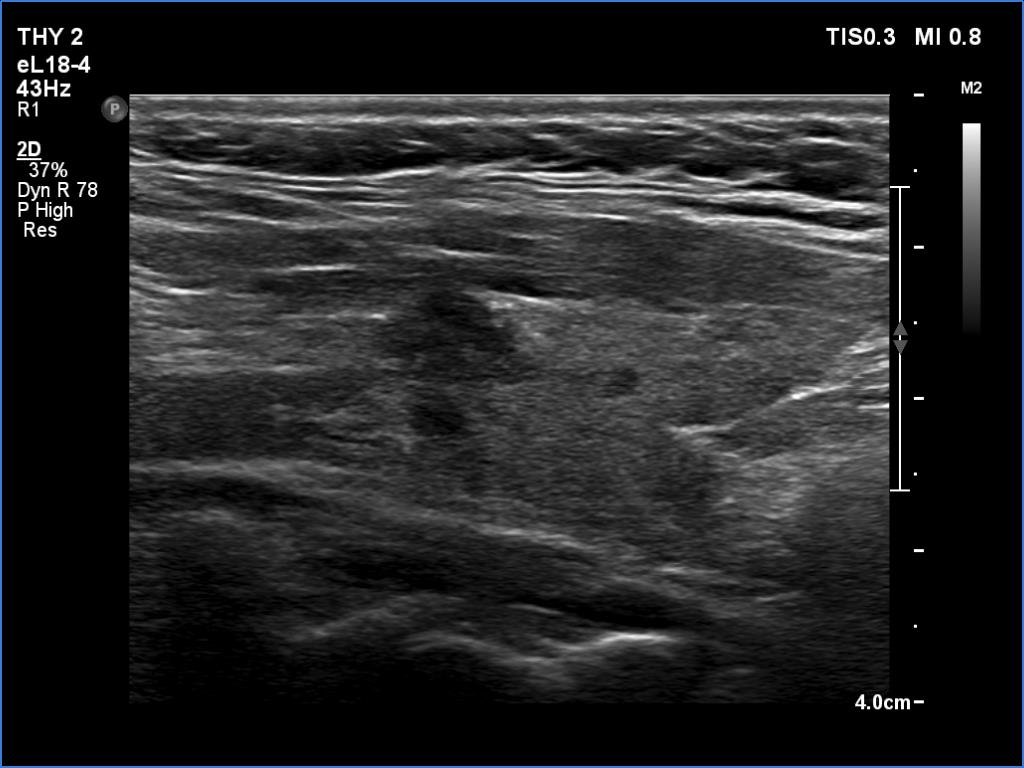

Lymphocytic thyroiditis - case 188

Follow-up investigation 2 years after the first visit (ultrasonographic picture 4)

Left lobe, longitudinal scan. The larger hypoechoic lesion remained unchanged.